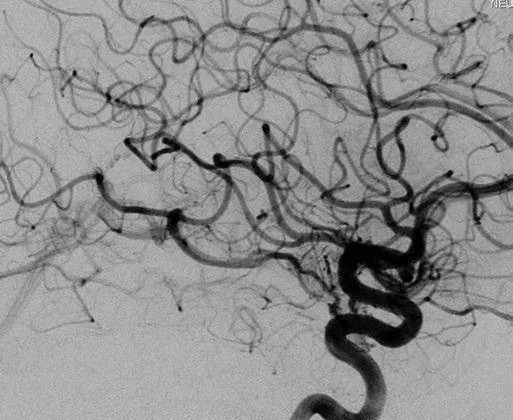

颞叶内侧少量残留畸形团向BVR引流(右ICA造影,侧位)

然而,就在伽马刀治疗 3 年后,造影显示AVM大部分闭塞,颞叶内侧少量残留畸形团向 BVR 引流。